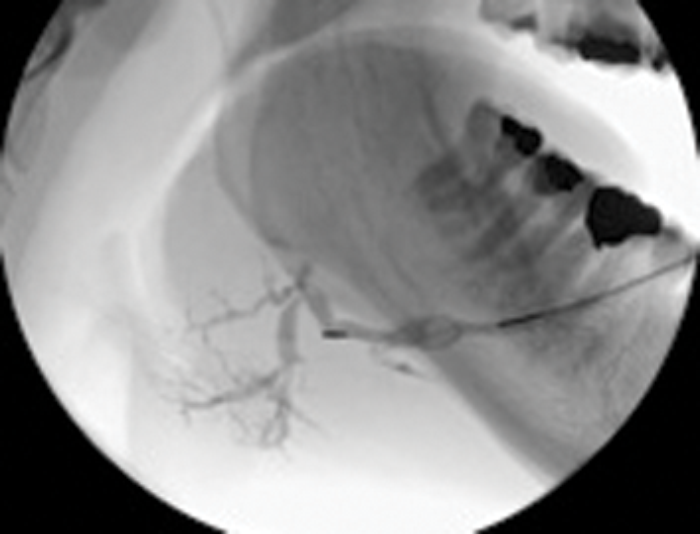

Figure 3: (C) The stone trapped in the open basket.